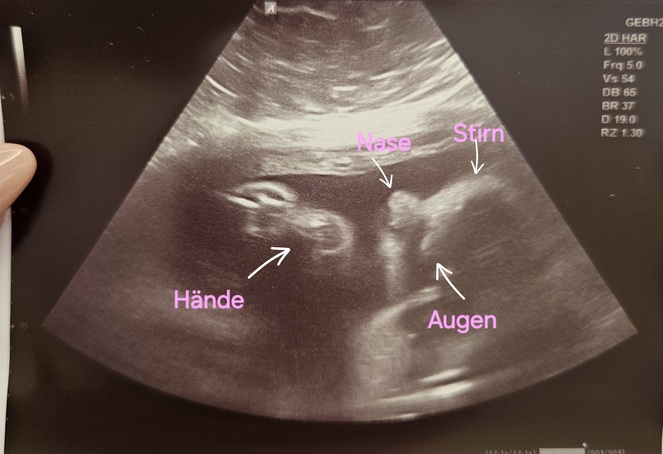

3. Ultraschall und weiterhin kamerascheu - Tagebücher aus der Schwangerschaft von Marie aus bei Heidelberg

Eine neue wunderbare, aufregende und vielleicht auch lang erwartete Lebenszeit beginnt. Für unsere Tagebücher-Blogs haben wir immer 3-4 schwangere Frauen in unterschiedlicher Schwangerschaftsphase, die in freudiger Erwartung über jede Woche dieser spannenden Zeit schreiben, uns und die vielen tausend Follower:innen daran teilhaben lassen und damit unvergessliche Momente schaffen.